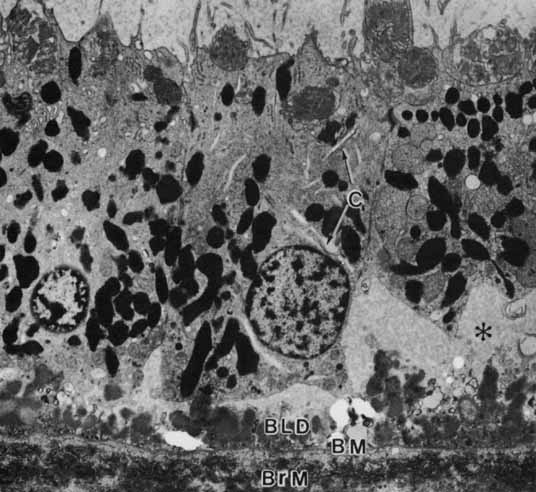

Age-related macular degeneration (AMD) is the leading cause of blindness among adults. Although the specific causes of AMD remain unknown, these include a combination of intrinsic (i.e., genetic predisposition) and extrinsic (i.e., environmental insult such as toxic and/or photooxidative damage) factors that have their primary impact on the RPE.71 AMD is associated in its early phases with the buildup of incompletely metabolized waste products in association with the RPE, both intracellularly (i.e., lipofuchsin) (Fig. 17) and extracellularly (i.e., drusen) (Figs. 18 and 19). Subsequent malfunction of the RPE proper, and/or Bruch's membrane, lead to the progression of AMD from its “dry” state with damage to the RPE and neural retina, wherein the focus of the lesion remains at the RPE/neural retina interface, to the “wet” state wherein signals that possibly originate with the RPE result in abnormal responses in surrounding tissues resulting in neovascularization in the choriocapillaris.72 Evidence to support the “toxic accumulation” hypothesis has come from studies of Stargardt's disease, a form of juvenile macular degeneration, whereby a primary defect of lipid metabolism in the neural retina leads to accumulation of toxic products following their uptake by the RPE, whose failure then subsequently leads to photoreceptor loss.73

Fig. 18 Basal surface of the retinal pigment epithelium of the macula of a 69-year-old woman. The basement membrane (BM) has been penetrated by lipid vesicles (LV) emanating from the epithelium. Deposition of material with 100-nm periodicity (arrows) increases the distance between the epithelium and its normal basement membrane. The focal adhesion (FA) exists between the epithelium and this newly deposited material (El, elastic lamina of Bruch's membrane; ×24,500).

Fig. 19 Macular retinal pigment epithelium of a 97-year-old woman showing the basal linear deposit (BLD) internal to the basement membrane (BM). The retinal pigment epithelium has no basal infoldings and no apparent attachment foci to anchor the cells to Bruch's membrane. Clefts (C) in the cytoplasm may be elements of the Golgi apparatus. The asterisk marks subretinal pigment epithelial proteinaceous fluid (Ph, phagosome; ×4,600).